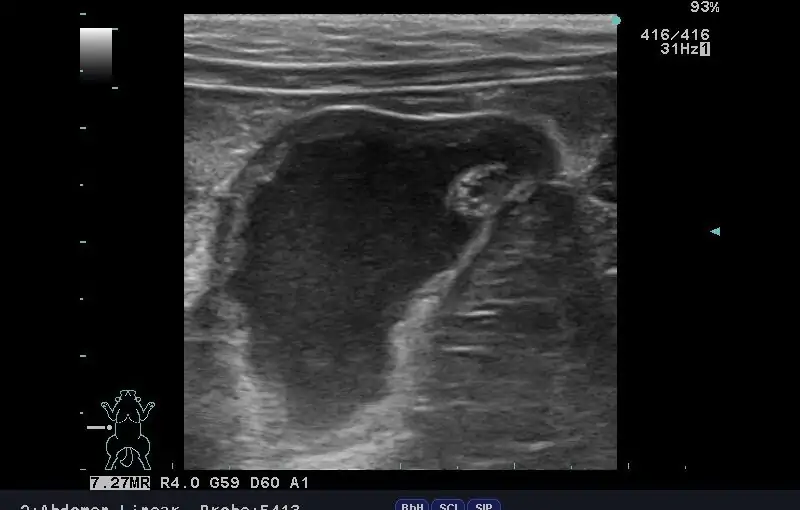

2025/09/24 放っておくと命の危険も!『子宮蓄膿症』ってどんな病気? ⚠️ ご注意くださいこの投稿には、手術中の写真や臓器・血液を含む画像が掲載されています。医療的な内容にご関心のある方向けの投稿となっておりますので、出血や臓器の画像が苦手な方は、閲覧をお控えください。 今回は、避妊手術を […] MORE